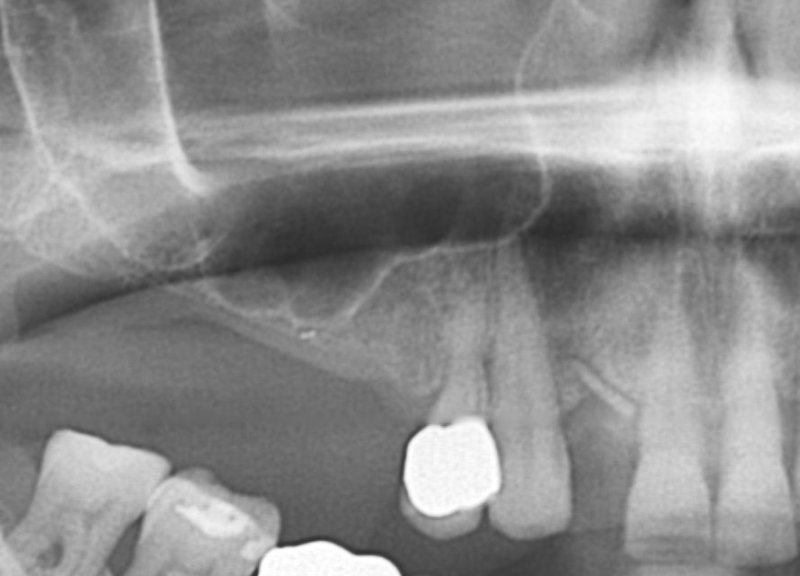

01/20 - Pre-operative x-rayGBR with maxresorb® & Jason® membrane - Prof. Dr. Dr. D. Rothamel

-